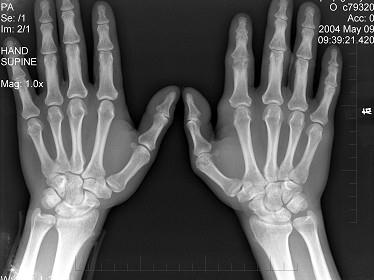

男,19岁,双手肿痛2年,晨僵,结合图像,最可能诊断是?(?)A.痛风B.强直性脊柱炎C.类风湿关节炎D.退行性关节炎E.未见异常

问题 男,19岁,双手肿痛2年,晨僵,结合图像,最可能诊断是?(?)

选项 A.痛风 B.强直性脊柱炎 C.类风湿关节炎 D.退行性关节炎 E.未见异常

答案 C